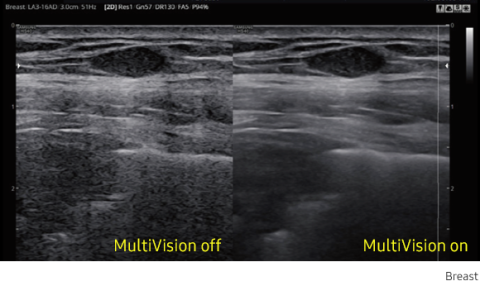

MultiVision controls ultrasound beam electronically by steering, and compounds many scan lines for better image. MultiVision provides remarkable spatial and contrast resolution with even greater artifact suppression than ever before.